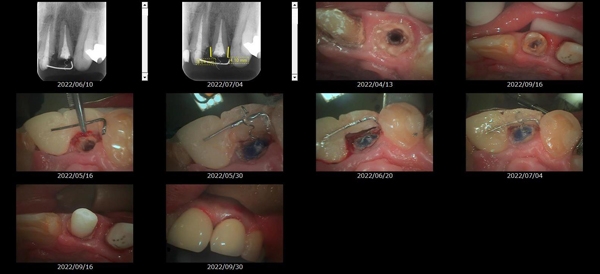

救歯MTM

虫歯が大きくて残せない歯、転倒などの事故により歯が根の深いとこで折れてしまったなどで、抜かざるを得ない歯を、骨の中に埋まっている健全な根を、骨の上に矯正的に引き上げることで、その歯を抜かず温存、救歯できる可能性のある治療方法です。

①健全な歯を、歯肉から見える位置にまで引き上げることで

根の治療の成功率を上げることが出来る。唾液には沢山の細菌がいます。唾液が入らない環境での根の治療を(神経の治療)を行うことで神経の治療、根の治療の成功率は格段と上がります。

②骨の上にある歯と土台で支える被せもの製作できる。

被せものを土台だけに頼ることなく、引き上げた健全な歯でも支えることで、歯への被せ物がしっかりと装着できるようになる。

③抜かずに歯を活かすことで、隣の歯を削るブリッジやインプラントにしないで済むことがある。

歯を矯正的に引き上げることで、その歯を救歯できるだけでなく、隣の歯を削るなどの侵襲を回避できる場合がある。

救歯治療と審美性の両立

当院では様々な治療の基礎に審美と機能の両立というテーマがあります。

症例